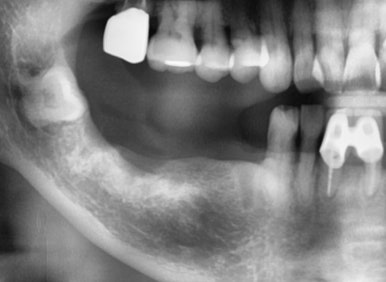

아쉽지만 기존 임플란트를 살려서 쓰는 것은 문제가 있다고 판단하여,

임플란트 제거 후에 다시 식립하는 것으로 치료계획을 설명드리고, 치료를 진행하였습니다.

현재 상태에서 임플란트 제거와 동시에 재식립하는 것은 무리라는 판단이 들어,

충분히 기다렸다가 염증도 가라앉고 잇몸이 어느정도 회복이 이루어지고 나면 수술하는 것으로 결정하였습니다.